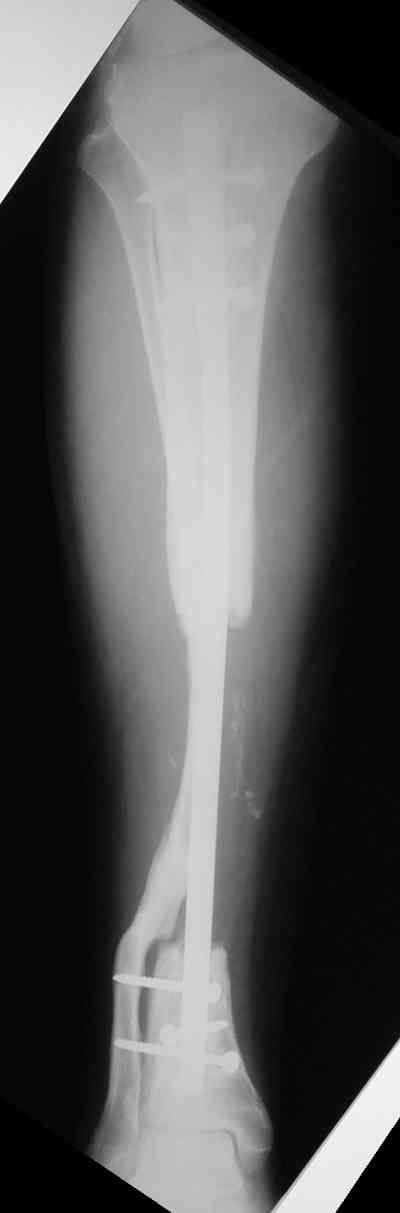

Владимир, свободная костная пластика на фоне свища вряд ли оправдана. Почему не рассматриваете вариант транспорта кости по Илизарову? Что собираетесь делать с латентной инфекцией? Одни антибиотики не помогут, необходима полноценная хирургическая обработка, Мы бы подумали о цементном спейсере с антибиотиками, бусах. После купирования инфекции переходить к замещению

дефекта: за счет удлинения концов б\б кости или тибиализации м\б. На начальном этапе фиксация только в аппарате, в последствие для удержания достигнутого можно перейти на фиксацию интрамедуллярным штифтом (см. вложенные файлы)

Доводим также к сведенью что дистальный межберцевый синастоз уже состоялся, ложный сустав малоберцевой кости в с/з. Учитывая так же отсутстаие нормального обеспечения больного в послеоперационном периоде мы склоняемся к аппарату внешней фиксации.

Как дополнение высылаю снимки и фото конечности, чтобы Вы могли оценить состояние м/т, и течение заболевания.

Кстати на предоперационных снимках видно, что Ваш пациент имел Сегментарный перелом на границе верхней и средней трети большеберцовой кости и средней трети большеберцовой кости. Непонятно почему был удалён средний сегмент перелома.Почему в течении такого большого времени не предпринимались попытки для замещения деффекта.

Судя по месту расположения свища, наличия литического учаска в проксимальной части дистального фрагмента на последнем снимке, и, наличие в этом месте стержня Шанца на послеоперацционном снимке, причина остеомиелита у Вашего пациента спицевая.